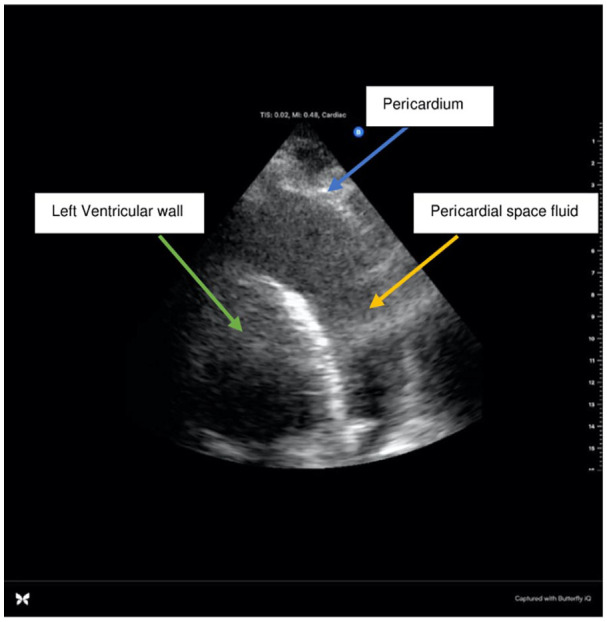

Pericardial effusions, though relatively rare, can lead to life-threatening complications such as cardiac tamponade. While viral etiologies are common culprits, rapid and accurate diagnosis remains challenging. We present the case of a 74-year-old male with a history of upper respiratory infection who developed sudden onset dyspnea and chest discomfort. Bedside point-of-care ultrasound (POCUS) revealed a large pericardial effusion, prompting urgent intervention. Despite initially stable vital signs, the patient rapidly deteriorated, necessitating emergent pericardiocentesis. Laboratory findings and pathology results eventually ruled out common viral causes, guiding diagnosis toward coxsackieviruses A and B, echovirus, adenoviruses, or influenza. This case highlights the critical role of POCUS in resident-led community hospitals, in expediting the diagnosis of pericardial effusions and underscores the need for prompt intervention in cases of cardiac tamponade to prevent adverse outcomes.